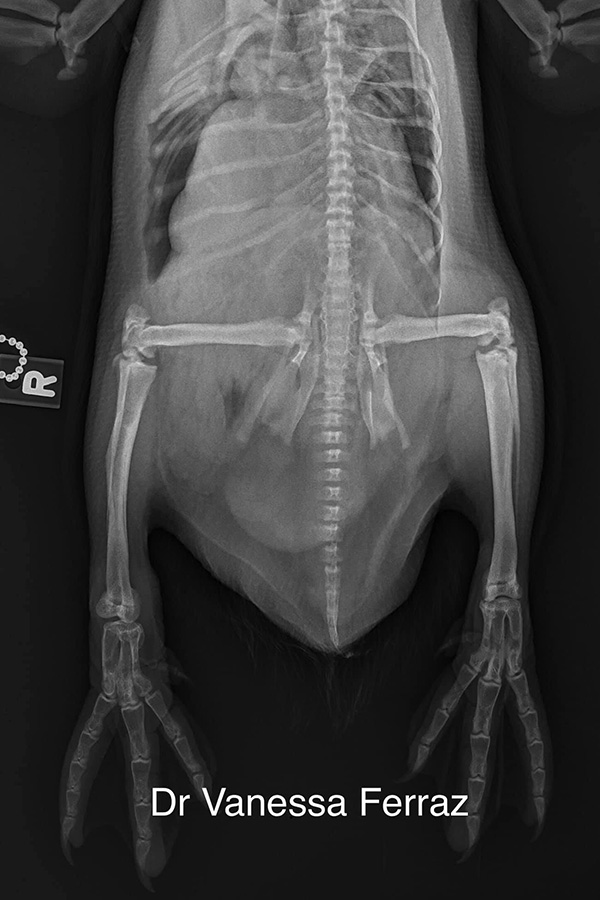

“This young zoo penguin had what avian people call a slipped tendon: a subluxation of the tibiotarsus-tarsometatarsus joint, which made it very difficult for him to walk,” says Ferraz, who practices veterinary medicine in both Gainesville, Florida, United States, and São Paolo, Brazil, and is a member of the AO VET Latin America Regional Board. “I went to take a look at the penguin and said, ‘Let’s give it a try,’ because the consequences of not trying can be very serious. If the animal can’t walk, it probably would be euthanized.”

Additionally, because penguins are a “top-heavy” species, they face pain and suffering with a slipped tendon. The problem is more frequent in production chickens and Ferraz hypothesizes that it’s due to the animals growing too fast but could be caused in chickens and other birds by genetics or even infection.